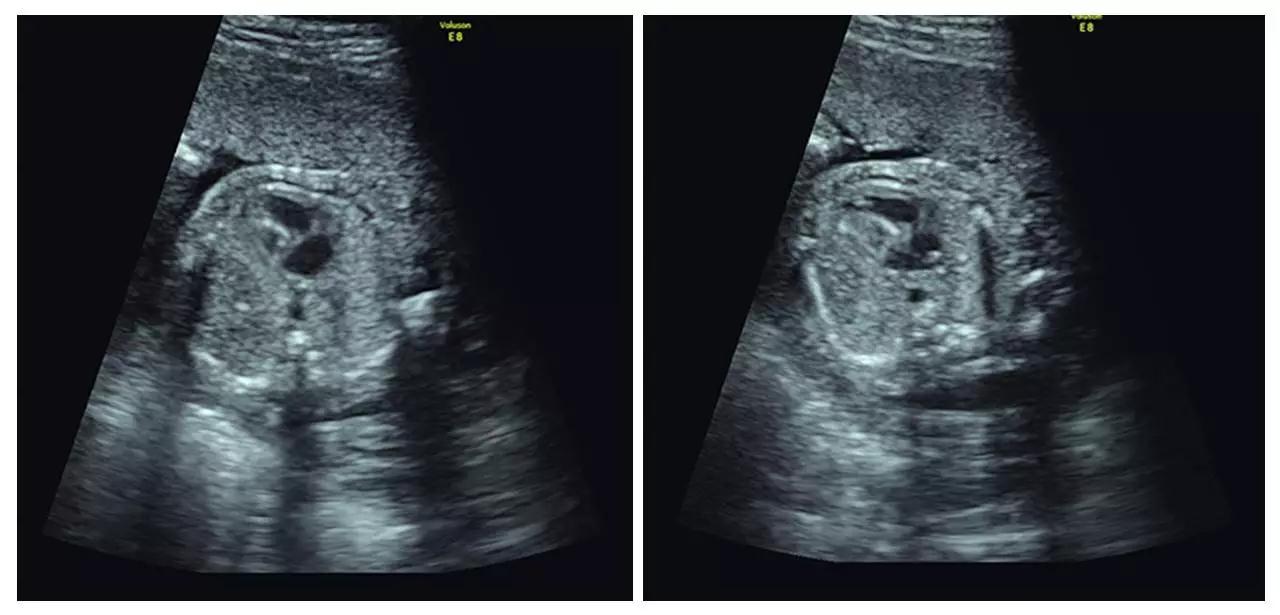

(颈后水囊瘤)

(胎儿左手未见,考虑截肢畸形)

(胎儿颅内结构异常、眼距窄、鼻结构异常...)

以上案例更多的是警示我们四维彩超(四维彩超)检查的重要性。我们希望每个宝宝都能健康成长。